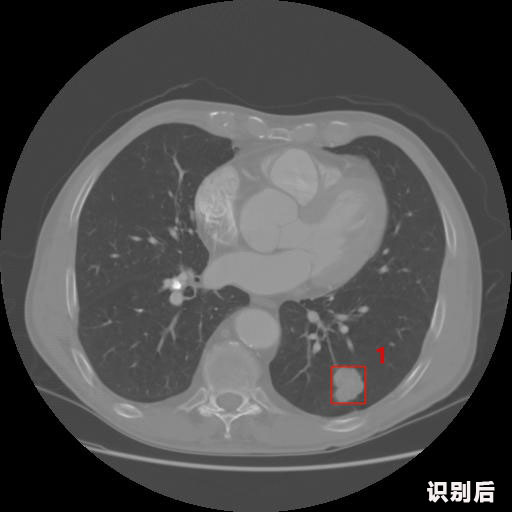

英特健康AI深度學習醫(yī)療圖像識別系統(tǒng)案例_胸部CT

1.發(fā)現(xiàn)肺結節(jié)的可能性為95.56%---位于框指數(shù)位置:[331.70554 366.13406 365.21707 403.96234]